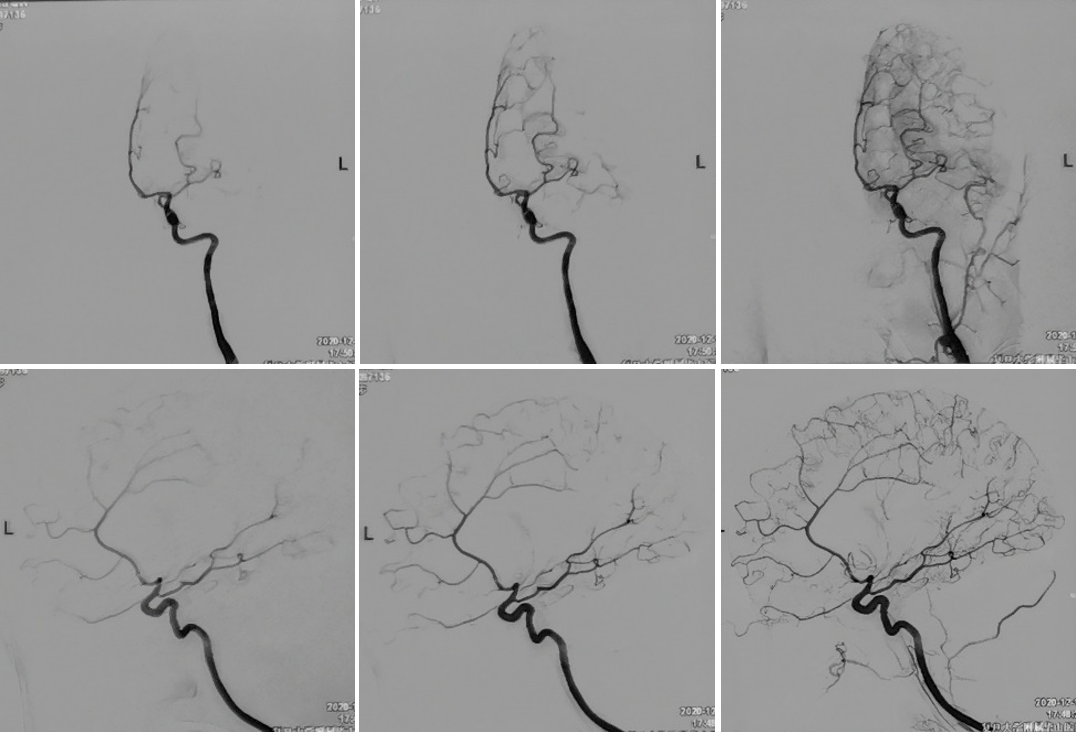

2020-12-16 post-op CT

术中电生理未见明显异常,因此未进行进一步血流重建处理。